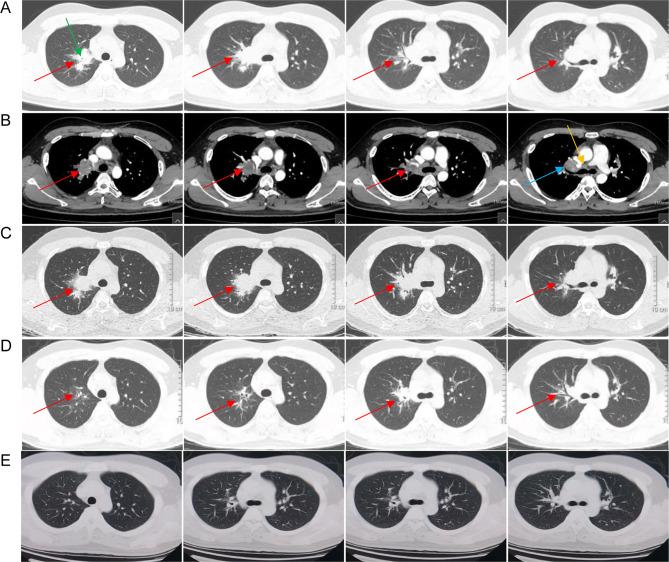

is a nonpathogenic pathogen commonly found in nature and is generally considered a contaminant in clinical practice. Although there have been few reported cases of infection, most of them are secondary to immunosuppression. This paper described a rare case of globular shadow in the chest of an immunocompetent male who was diagnosed with pulmonary disease. He went to the hospital with chest pains that had lasted for more than two weeks. The routine clinical pathogen detection failed to discover the cause of the infection. Although metagenomic next-generation sequencing (mNGS) of the lung tissue was negative, was detected in the background microorganism with only one read. Based on the pathological results, it was considered to be the causative pathogen. Two months of treatment with rifampicin, ethambutol, clarithromycin, and levofloxacin resulted in significant reduction and absorption of lung lesions. No abnormalities were detected in either lung one year later. The lack of positive culture and other conventional microbiological test results make this case is not a strictly confirmed case. This study also explored the clinical features and treatment options of 32 cases of pulmonary disease through a systematic review of the literature. Although there is no standard recommended treatment regimen for infection, but combination therapy with macrolides, rifampicin, and ethambutol has been proven effective.

This case highlights that when the clinical highly suspected of infection, mNGS can contribute to the early identification of non-tuberculous Mycobacterium (NTM) even with low reads, when clinical suspicion is high. Analyzing background microorganisms in sterile samples may help diagnose rare pathogens.